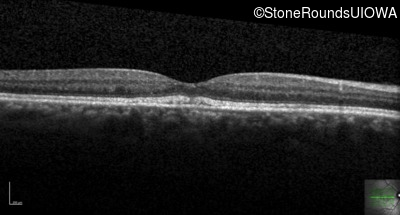

Optical Coherence Tomography - Right - 20/20 +2

Exemplar / OCT Stack

Optical Coherence Tomography - Left - 20/40 -2

Optical Coherence Tomography - Right - 20/20

Optical Coherence Tomography - Left - 20/63

Optical Coherence Tomography - Right - 20/20 -2

Optical Coherence Tomography - Left - 20/50